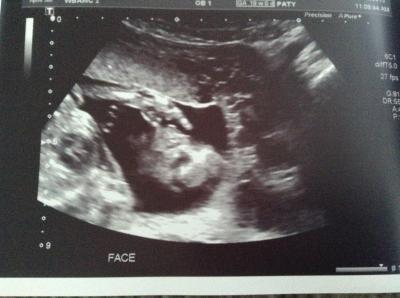

War heute auch beim organscreening und es ist soweit alles in Ordnung! Die Messungen ergaben auch alle ca der genauen ssw, teilweise ein zwei Tage kleiner! Größe und Gewicht haben wir leider nicht erfahren, aber es war alles dran! Da wir jetzt umziehen war das auch der letzte Termin, ich darf aber morgen meine medical Records abholen, Vllt stehen da noch genauere Angaben drin! Ach und es wird übrigens ein junge! Mein Mann konnte sich kaum die Tränen verdrücken, er hat sich das so gewünscht! Der kleine Mann hat auch süß am Daumen genuckelt! So, heute ziehen wir jetzt noch hier in el Paso aus und dann geht's ab nach LA! Am 7 geht dann endlich der Flug zurück ins Geliebte Deutschland! Ich wünsche euch allen eine besinnliche Weihnachtszeit und einen guten Rutsch ins neue Jahr! Lg claudi und Baby Boy inside ;)

Bild zu Organscreening und outing - Forum für Mai - Mamis